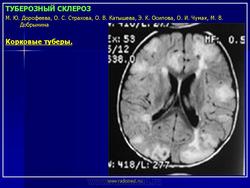

Наиболее типичными поражениями головного мозга при туберозном склерозе являются корковые туберы, субэпендимальные узлы и аномалии белого вещества мозга.

Корковые туберы различаются по своим размерам, локализации, консистенции и форме. Размер корковых туберов варьирует от нескольких миллиметров до нескольких сантиметров. Корковые туберы располагаются в виде выступов над единичной или прилегающими бороздами. Они расширяют борозду и сглаживают грань между серым и белым веществом. Туберы могут быть как единичными, так и множественными, имеют диффузную локализацию. Кальцификация туберов отмечается в 54% случаев и увеличивается с возрастом больных.

Своевременное выявление корковых туберов и кальцификатов мозга очень важно для диагностики туберозного склероза. Наибольшую значимость в верификации туберов при обследовании больных имеет магнитно-резонансная томография (МРТ), которая позволяет визуализировать туберы в 95% случаев.